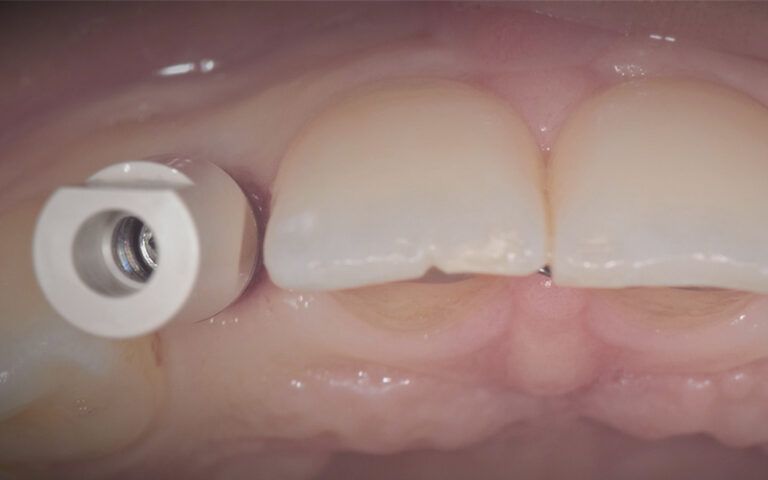

After three months of osseointegration, the second surgery performed on both implants and the digital impressions were taken with the TRIOS (3Shape) intraoral scanner.

Details of the digital impression with the scan abutments placed in the mouth Details of the digital impression with the scan abutments placed in the mouth Details of the digital impression with the scan abutments placed in the mouth

The impressions were sent to a reliable prosthetics laboratory to make provisionals while they worked on the CAD-CAM design and manufacture of the definitive zirconium crowns.